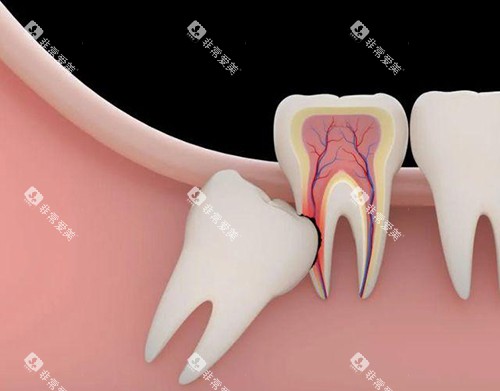

医院擅长的口腔治疗项目可多了,牙齿矫正、牙齿美白、根管治疗、牙齿种植等等,都能轻松应对。